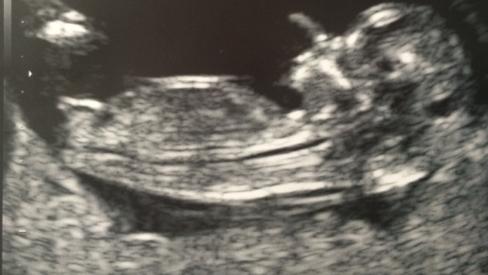

I thought I was 12 weeks but baby measured 12 weeks, 2 days... Please tell me your guesses!!! :)